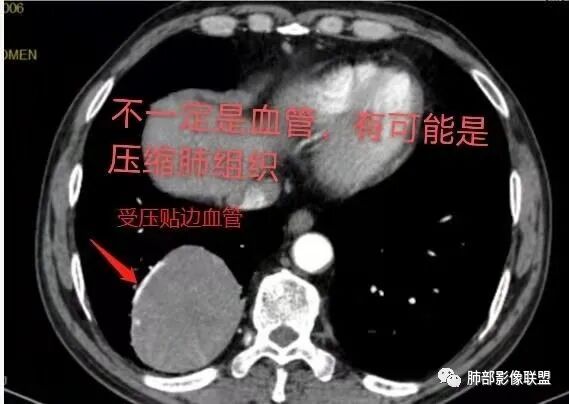

右肺下叶肿块,呈外带大内带小的椭圆形改变(内带受支气管及血管挤压原因),边缘光滑,无分叶毛刺,支气管受压,增强后,均匀延迟强化,动脉期见血管贴边,静脉期内部瘤样血管强化区,相邻胸膜无侵犯,纵隔无淋巴结肿大,符合PSP,不鉴别。

这条血管哪里来的?需要交代一下

这些是什么呢?

南边:

含气组织

常规肿瘤如果背侧胸膜来源,肿瘤与胸膜之间不应该夹杂含气支气管,会推移

但是肺内可以将支气管外推,夹在胸膜之间

与膈面胸膜类似推断

支持肺内

但是这条血管需要交代一下:

如果这是同一根肺动脉,支持PSP

因为肺门区来源肺动脉